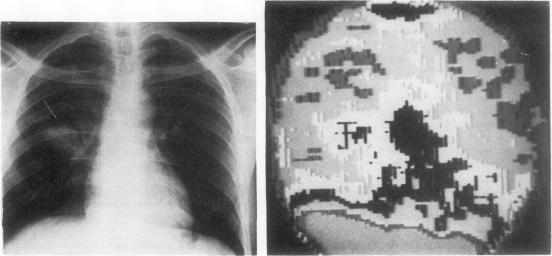

To establish or exclude the diagnosis of bronchial carcinoma a series of 43 patients with peripheral pulmonary opacities was studied by lung scanning after intravenous injection of 75Se-sodium selenite. A diagnosis was ultimately obtained in all patients. The incidence of both false-positive and false-negative results was high. Selenite was taken up by a range of non-neoplastic processes including inflammatory lesions. The value of the procedure in distinguishing bronchial carcinoma from non-neoplastic conditions of the lung that radiographically mimic carcinoma was not confirmed.

为了确立或排除支气管癌的诊断,对43例周围型肺实质模糊影患者在静脉注射75硒亚硒酸钠后进行了肺扫描研究。所有患者最终都得出了诊断结果。假阳性和假阴性结果的发生率都很高。亚硒酸盐可被一系列非肿瘤性病变摄取,包括炎症性病变。该检查方法在鉴别支气管癌与影像学上类似癌的肺部非肿瘤性疾病方面的价值未得到证实。